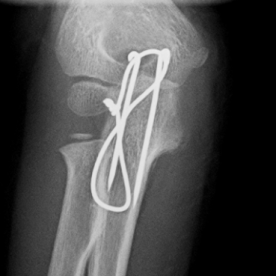

Röntgenbilder